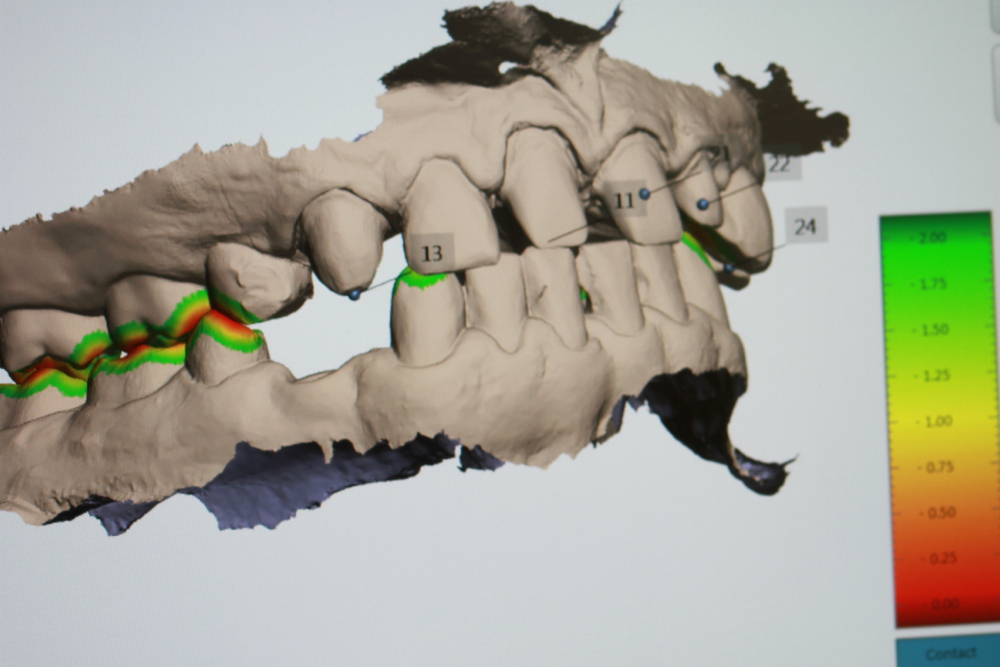

The management of complex dental rehabilitation requires careful planning and consideration of all the associated problems. When managing complex cases, it is usually necessary for other specialist clinicians to be involved in restoring the mouth to normal. This provides the best chance to correct any underlying problems that caused tooth destruction, and may reduce the amount of prosthetic work you require. We frequently work alongside other specialists such as Orthodontists, Periodontists, Endodontists and Maxillo-facial Surgeons to develop solutions to your individual problems.

Dr Parzham has an interest in the management of complex multi-disciplinary rehabilitations of severely broken down teeth.